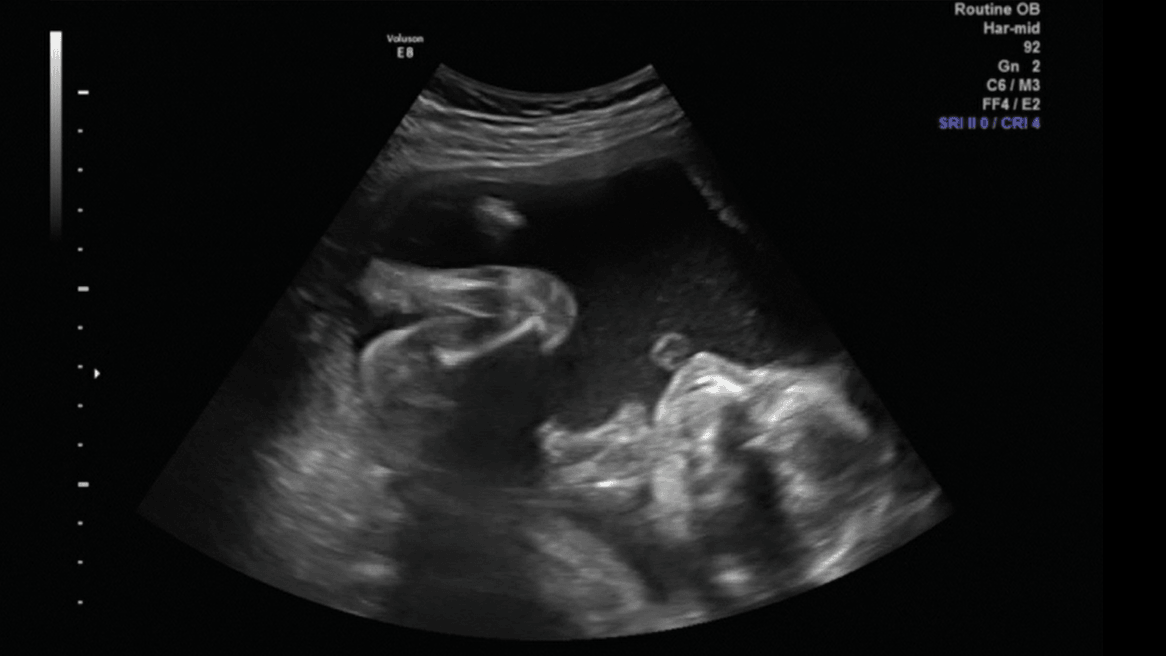

Porobiłam trochę screanów z usg połówkowego, więc pomyślałam, że wrzucę, mam nadzieję, że nie maci mi za złe ilości :D

Brzuszek, nóżki i klejnoty :D

2.png